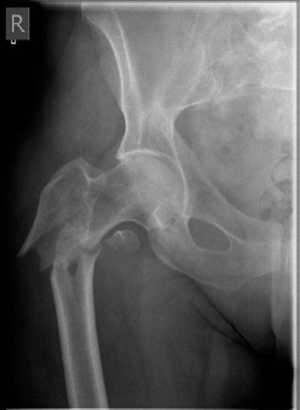

Lower limb Trauma Structured oral examination question 4 A 33-year-old roofer fell from a height of 20-feet, …